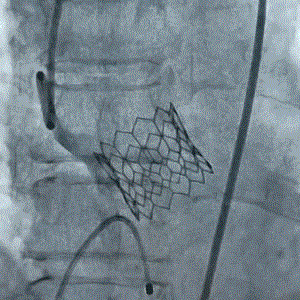

2021年9月27日,复旦大学附属中山医院魏来教授团队于博鳌外科网络直播了一例重度主动脉瓣狭窄、主动脉瓣二叶瓣(Type 1型)的经股动脉TAVI手术,这是佰仁医疗Renatus球扩式介入主动脉瓣首次在直播中登台亮相。 病例

9月27日上午10时,直播开始,魏来教授团队耗时约1小时,经右侧股动脉植入23# Renatus介入主动脉瓣。瓣膜植入位置理想,功能表现出色,造影及经食道超声观察显示瓣膜无中央性返流,轻微瓣周漏,无冠脉血流受阻,无传导阻滞,主动脉瓣峰值流速降至2.0m/s,平均跨瓣压差降至7mm/Hg。手术取得圆满成功。

本次手术直播的TAVI患者是瓣膜结构较为复杂的二叶式主动脉瓣畸形。这类病例主动脉瓣钙化重、形态不规则,选瓣难度大、定位要求高、并发症概率高。无论对术者的操作要求,还是对介入器械的质量要求,均比正常的三叶式主动脉瓣TAVI要高。本次患者手术成功再次证实了国产Renatus介入主动脉瓣的有效性、安全性和操控性均达到了设计要求,可以攻克主动脉瓣二瓣化畸形所带来的挑战。

佰仁医疗Renatus介入主动脉瓣系统,采用全球主流的球扩式设计,瓣架高度低、径向支撑力强,输送安全、定位精准,易于释放,结合多种入路的输送系统设计,适合各种路径的介入主动脉瓣置换术。并且基于该瓣膜支架的特殊纹理设计,日后可实现二次扩张,更有利于未来可能的瓣中瓣治疗。该瓣膜的设计与工艺实现了以本企业成熟的外科牛心包瓣同样的启闭模式与血流动力学特性,特别是加速疲劳测试验证了其与外科牛瓣相同的耐久性;采用经长期临床验证的抗钙化改性处理的牛心包为瓣叶材料,使该产品顺利通过全性能注册检验和动物实验验证,目前已启动国内多家知名心脏中心的正式临床试验。该临床试验正面向社会招募患者,为更多类似需要救治的危重患者提供救治机会。